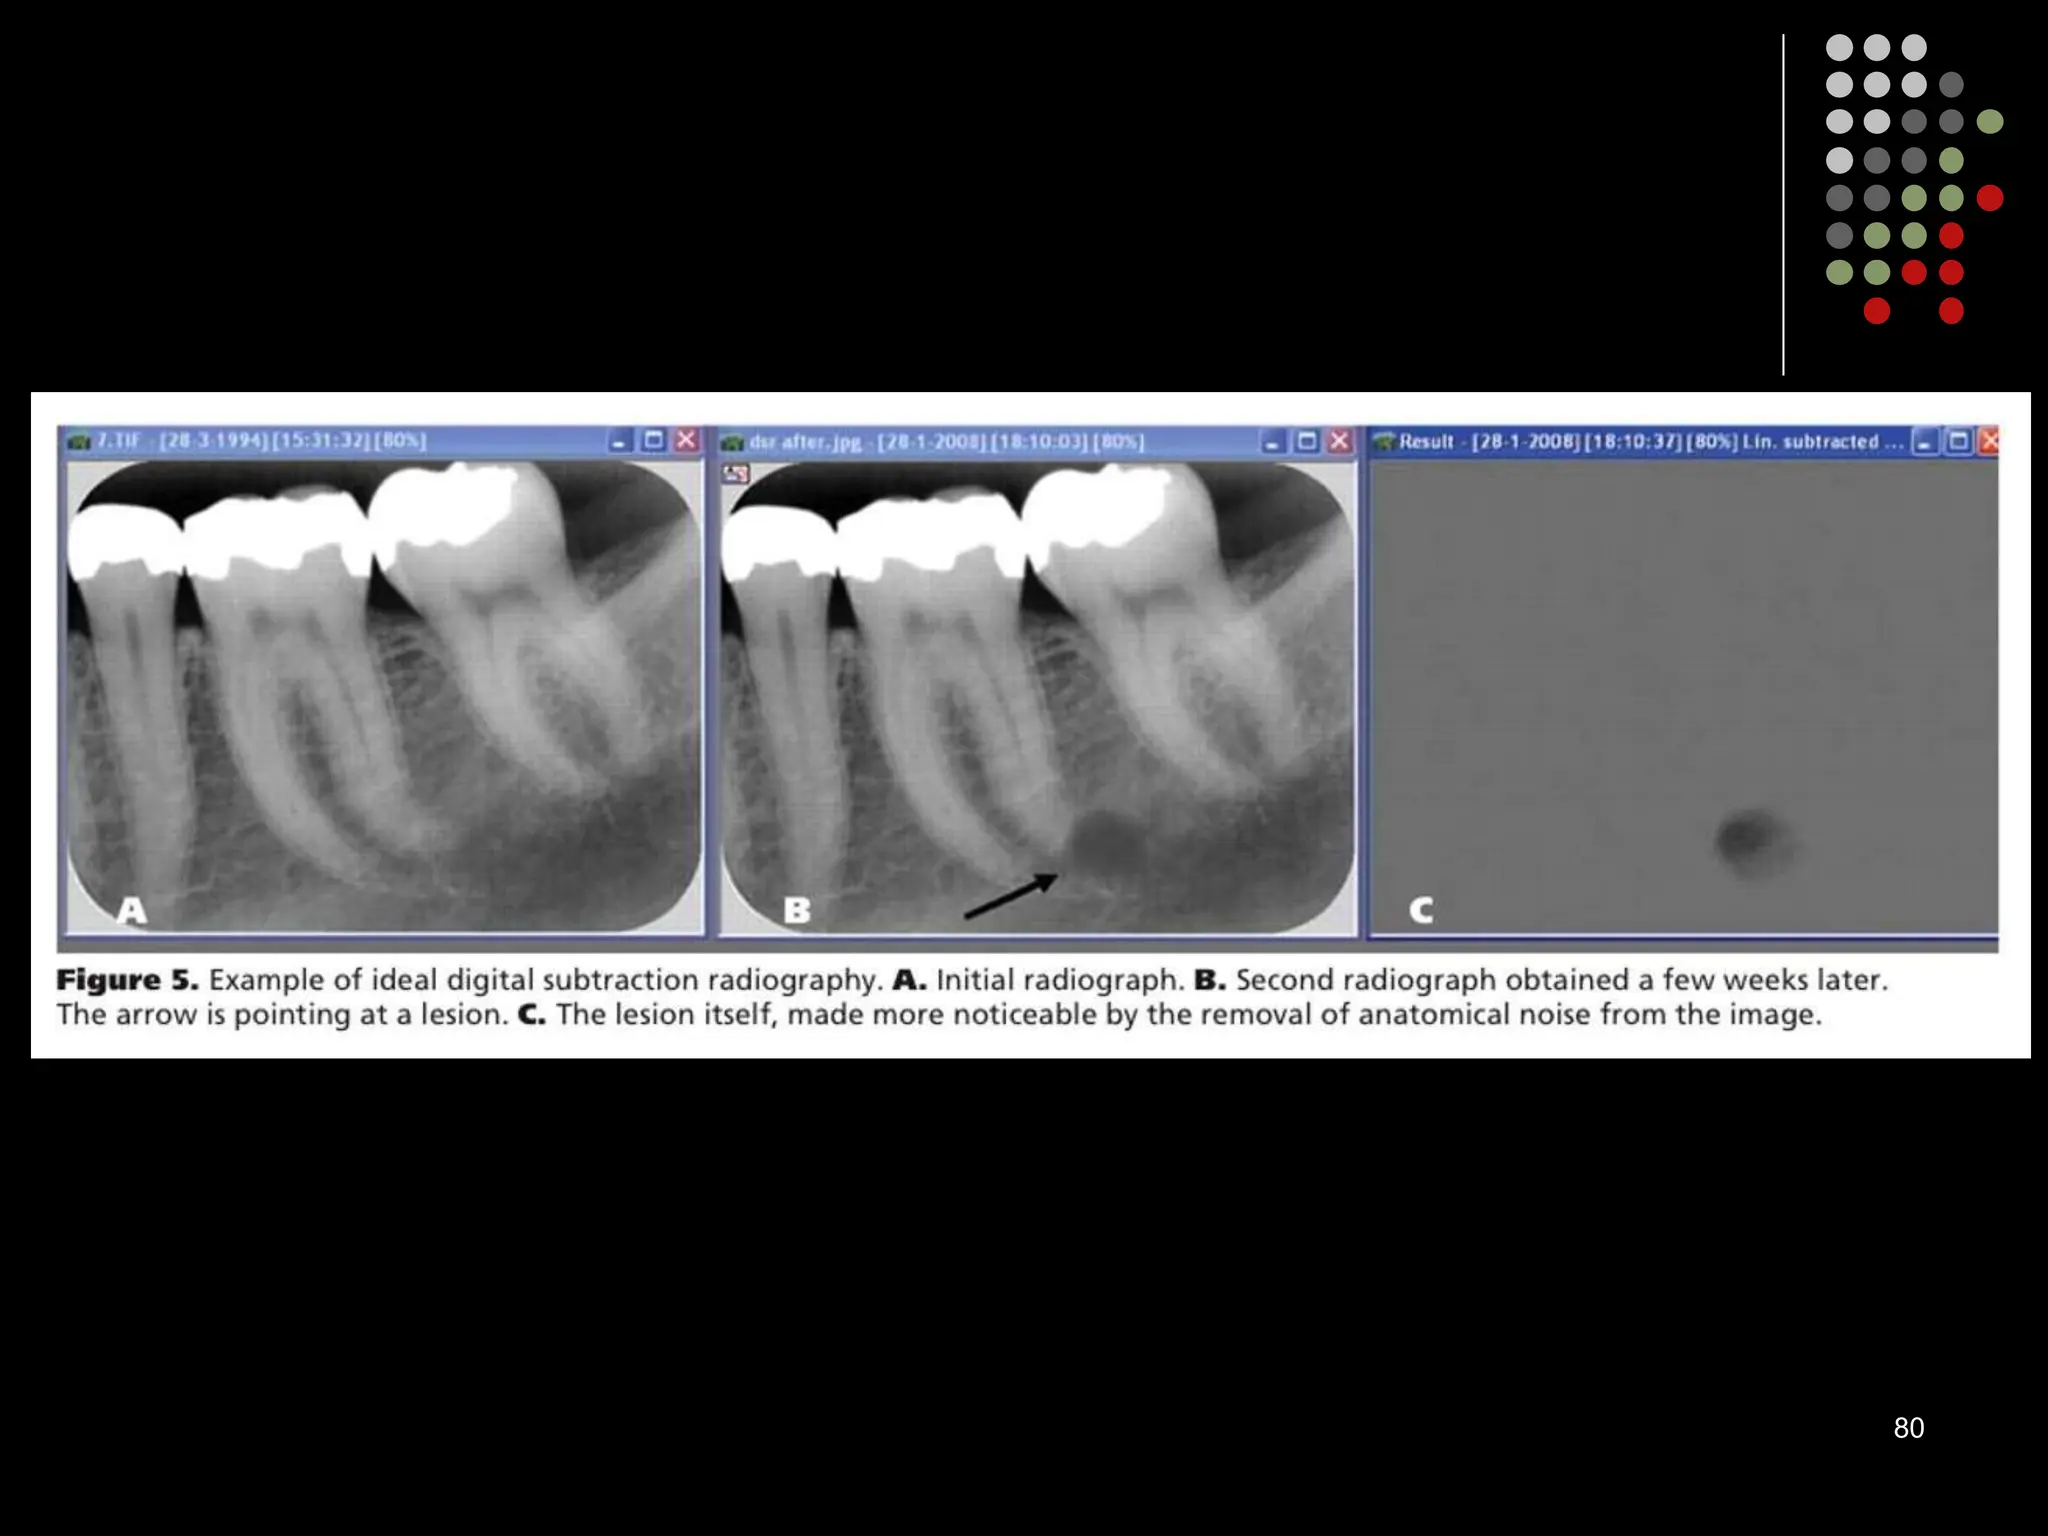

Digital subtraction radiography

 Subtraction in digital radiology is another image enhancement method with purpose

to produce two radiographs of the same area in the mouth at the different time

intervals.

 The first image can be subtracted from the second one to identify changes that may

have occurred during a certain time period. Minimal changes in loss or gain of hard

tissue can be detected using this technique, otherwise undetectable by visual

examination and traditional radiography.

79

80